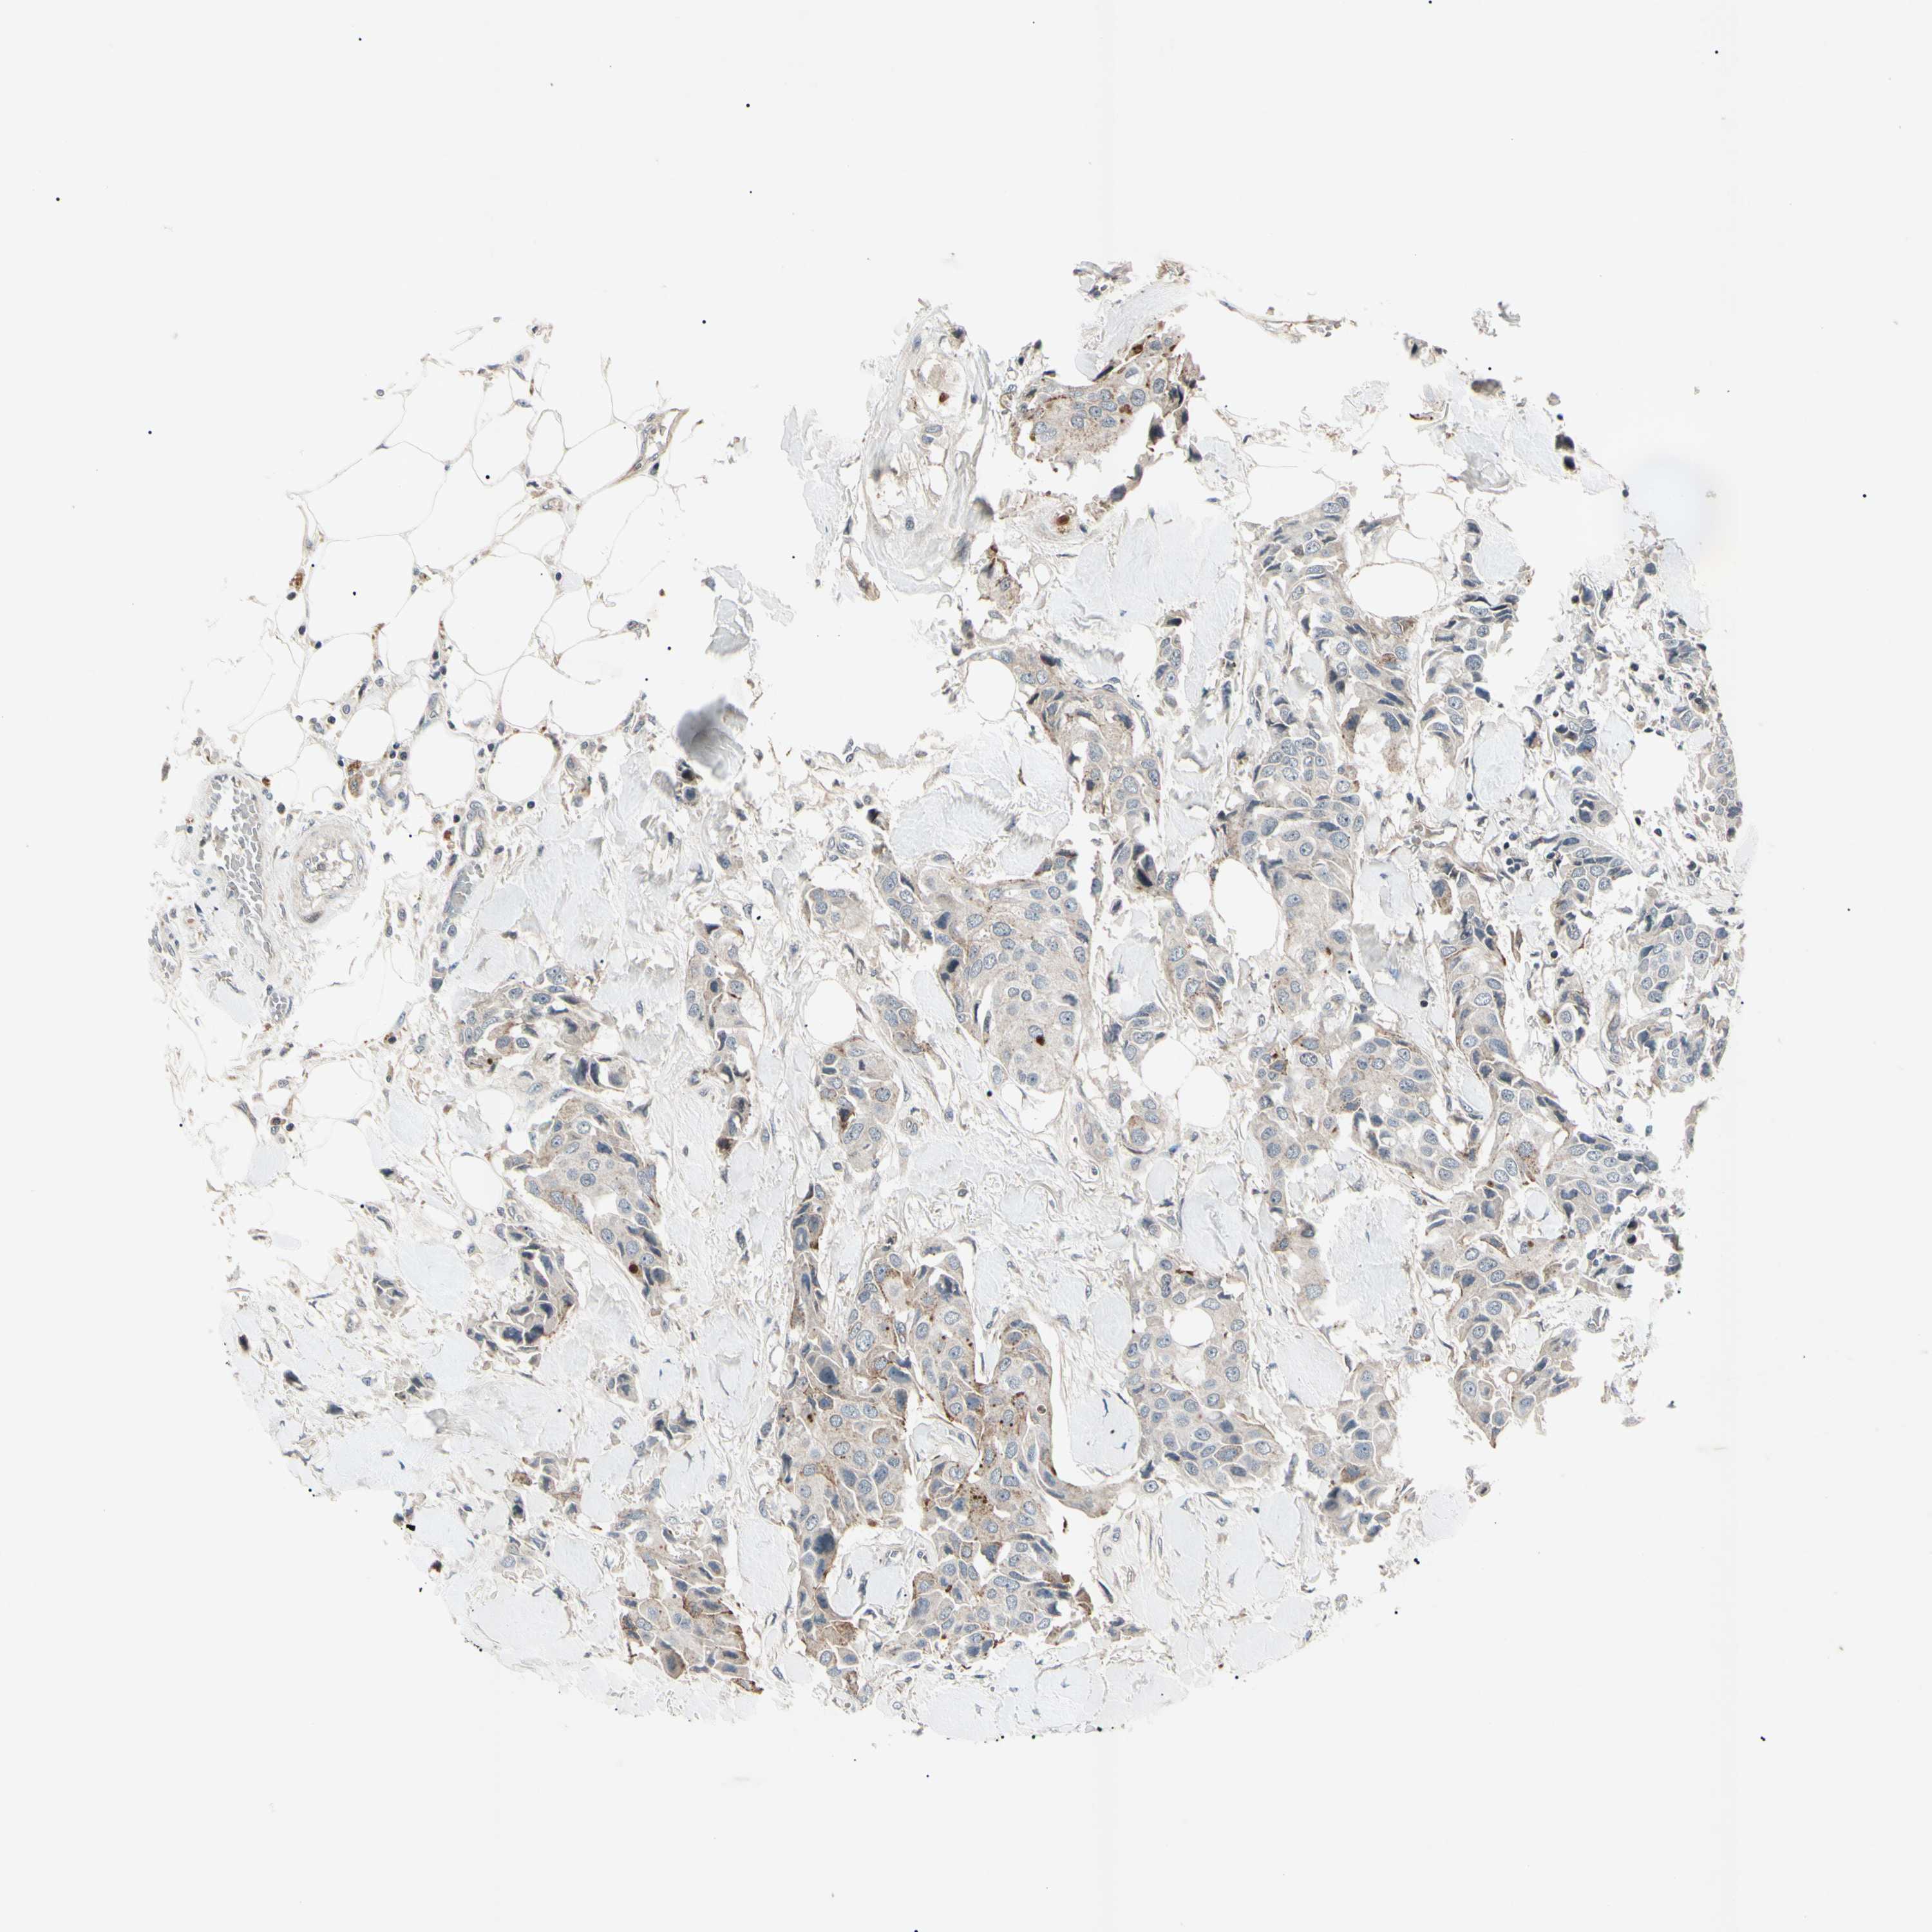

BRCA TCGA BRCA VALIDATION PROTEIN EXPRESSION